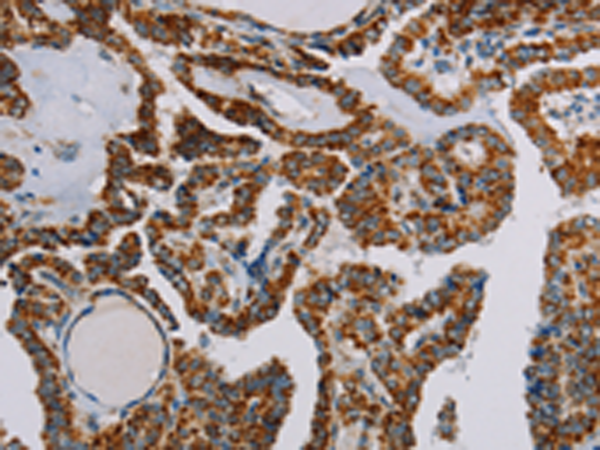

分类: 科研抗体货号: P01531别名: MORG1应用: WB,IHC反应种属: Human, Mouse, Rat

分类: 科研抗体货号: P01583别名: CI-30应用: WB,IHC反应种属: Human, Mouse

分类: 科研抗体货号: P01580别名: B8; CD14; CIB8; MC1DN13应用: WB,IHC反应种属: Human, Mouse

分类: 科研抗体货号: P01606别名: NS; E2IG3; NNP47; C77032应用: WB,IHC反应种属: Human

分类: 科研抗体货号: P01655别名: MPPB; P-52; MPP11; MPPP52; Beta-MPP应用: WB,IHC反应种属: Human, Mouse, Rat

分类: 科研抗体货号: P01604别名: CN1; CNI; CN-I; CN1A; CN-IA应用: IHC反应种属: Human, Mouse